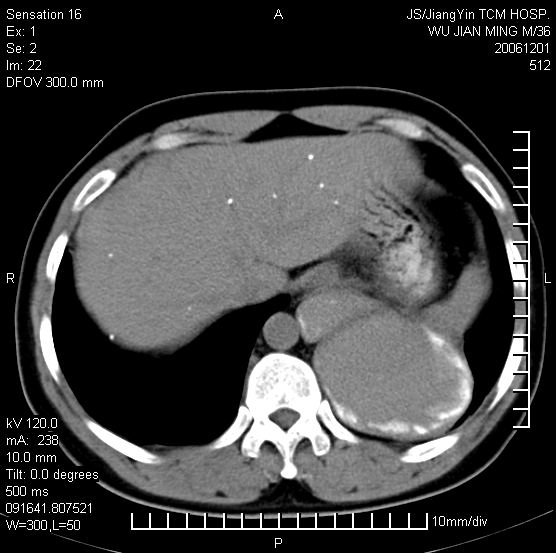

以下是引用dyqct在2006-12-1 21:17:00的发言:[br]左心缘旁及后肋膈窦区见巨大椭圆形混杂密度肿块,周围见大小不等斑片状钙化,内部无强化,周围包膜轻度强化,心脏明显受压变形,即明显占位效应,肿块广基与心包、膈相连。肝、脾内、肝门见多数小结节状钙化影。[br]考虑:1、左心缘旁及后肋膈窦区慢性包裹性胸膜炎(结核性);[br] 2、肝、脾及肝门淋巴结核已钙化。[br]

以下是引用zyx168在2006-12-2 10:10:00的发言:[br][br]肝脾肺内多发钙化灶